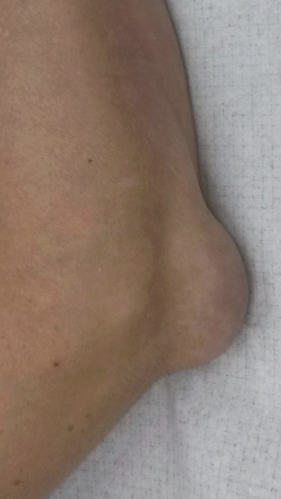

Рецидивирующий бурсит коленного сустава

Излечение за 2 процедуры ФДТ Ревиксан

Параметры изменяются в зависимости от процедуры

Дата публикации: 17.11.2025 11:31:27